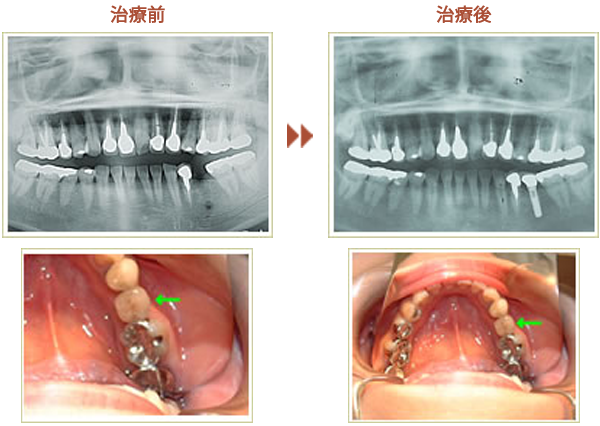

歯を数本失った場合

症例 60歳 男性 インプラント埋入数:6本